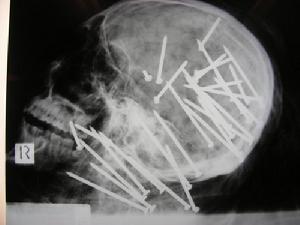

澳大利亞警方公布了劉辰頭部X光片劉辰,男,27歲,中國公民,於2000年由中國以學生簽證入境移民至澳大利亞第二大城市墨爾本,2005年再由墨爾本市移居到悉尼。

公布X光照片

2009年12月9日,據法新社報導:澳大利亞警方為了追緝兇徒,已向社會發放死者頭顱的X光照片。照片顯示,兇徒殺人手法極度兇殘,頭顱插滿34支鐵釘,部份鐵釘長達85毫米,基本全都嵌在腦殼上,讓人毛骨悚然。這張圖片震撼了全球人的眼球。